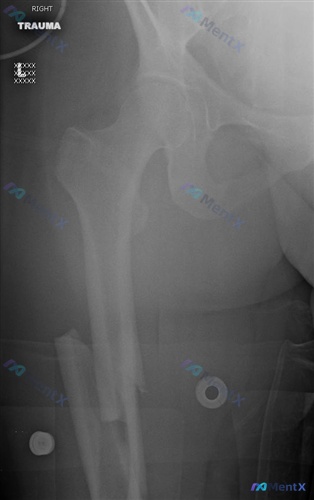

整理了一份昨天看到的股骨干骨折病例,关于手术入路的选择和并发症对比,觉得挺有代表性的,和大家分享一下思路。 --- 病例基本信息 - 患者:33岁女性 - 损伤类型:急性创伤(影像见图A) 影像核心表现(右侧大腿正位X光) 1. 骨折征象:右侧股骨干中下段可见明显骨皮质连续性中断,属于横断性骨折(伴...